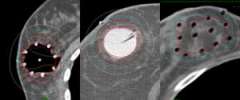

Partial breast irradiation (PBI) (fig 2&3)

• External Beam

• Balloon based implant

• Interstitial needle implant

• Intraoperative (IORT) – One treatment One day

Fig. 2: Partial breast external beam

Fig. 3: Partial breast brachytherapy (Balloon based and Implant based)